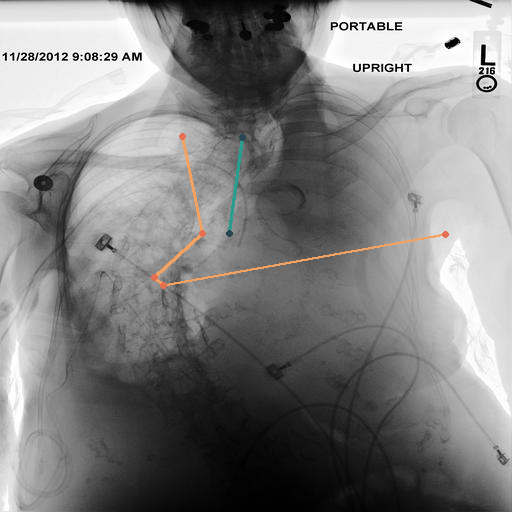

Automated Identification Cardio-Thoracic Ratio via CXAS

In Fig. 4, we show qualitative examples of the calculation of the cardio-thoracic-ratio for patients presenting cardiomegaly and not presenting cardiomegaly. For the case of the pathology, we see that the border of the heart is expanded, leading to a CTR above 0.7, whereas, for the absence case, the CTR is 0.4255.

When conducting a t-test, we get a value of 139.71 (p-value 0.0001) indicating a strong difference in CTR between positive and negative patients for cardiomegaly. We show this property in the violin plots on the left of Fig. 4, highlighting the CTR distributions for sex, age group, and pathology. Typically, the CTR for the presence and absence of cardiomegaly has noticeable shifts, with both respective means increasing with age. This average increase in CTR, however, becomes less in the age group of , with the disparity in mean CTR between cardiomegaly and no cardiomegaly reducing the older a patient gets. This result, in turn, lessens the insight of CTR with age. We observe this property for male and female patients. On the right of Fig. 4, we show the ROC-Curve for pathology classification based on the CTR score. We see a difference in the diagnostic performance of the CTR for female and male patients with an AuROC of 0.73 and 0.75.